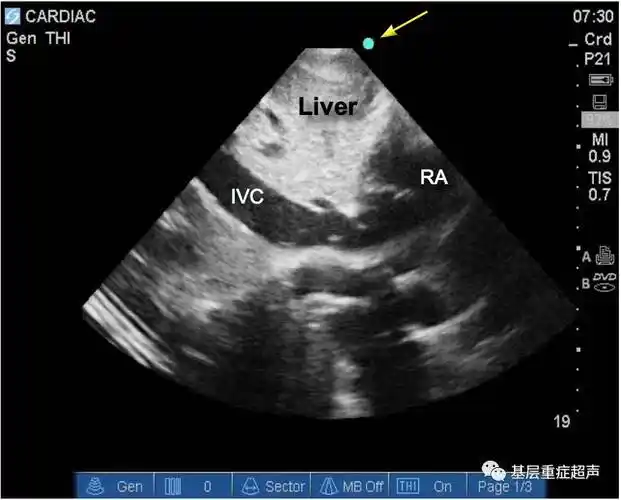

胸骨旁左心室短轴切面上魏相东读图谈心零基础入门心脏超声

重症超声胸骨旁短轴切面

超声心动图切面介绍胸骨旁长轴胸骨旁短轴心尖切面剑突下切面